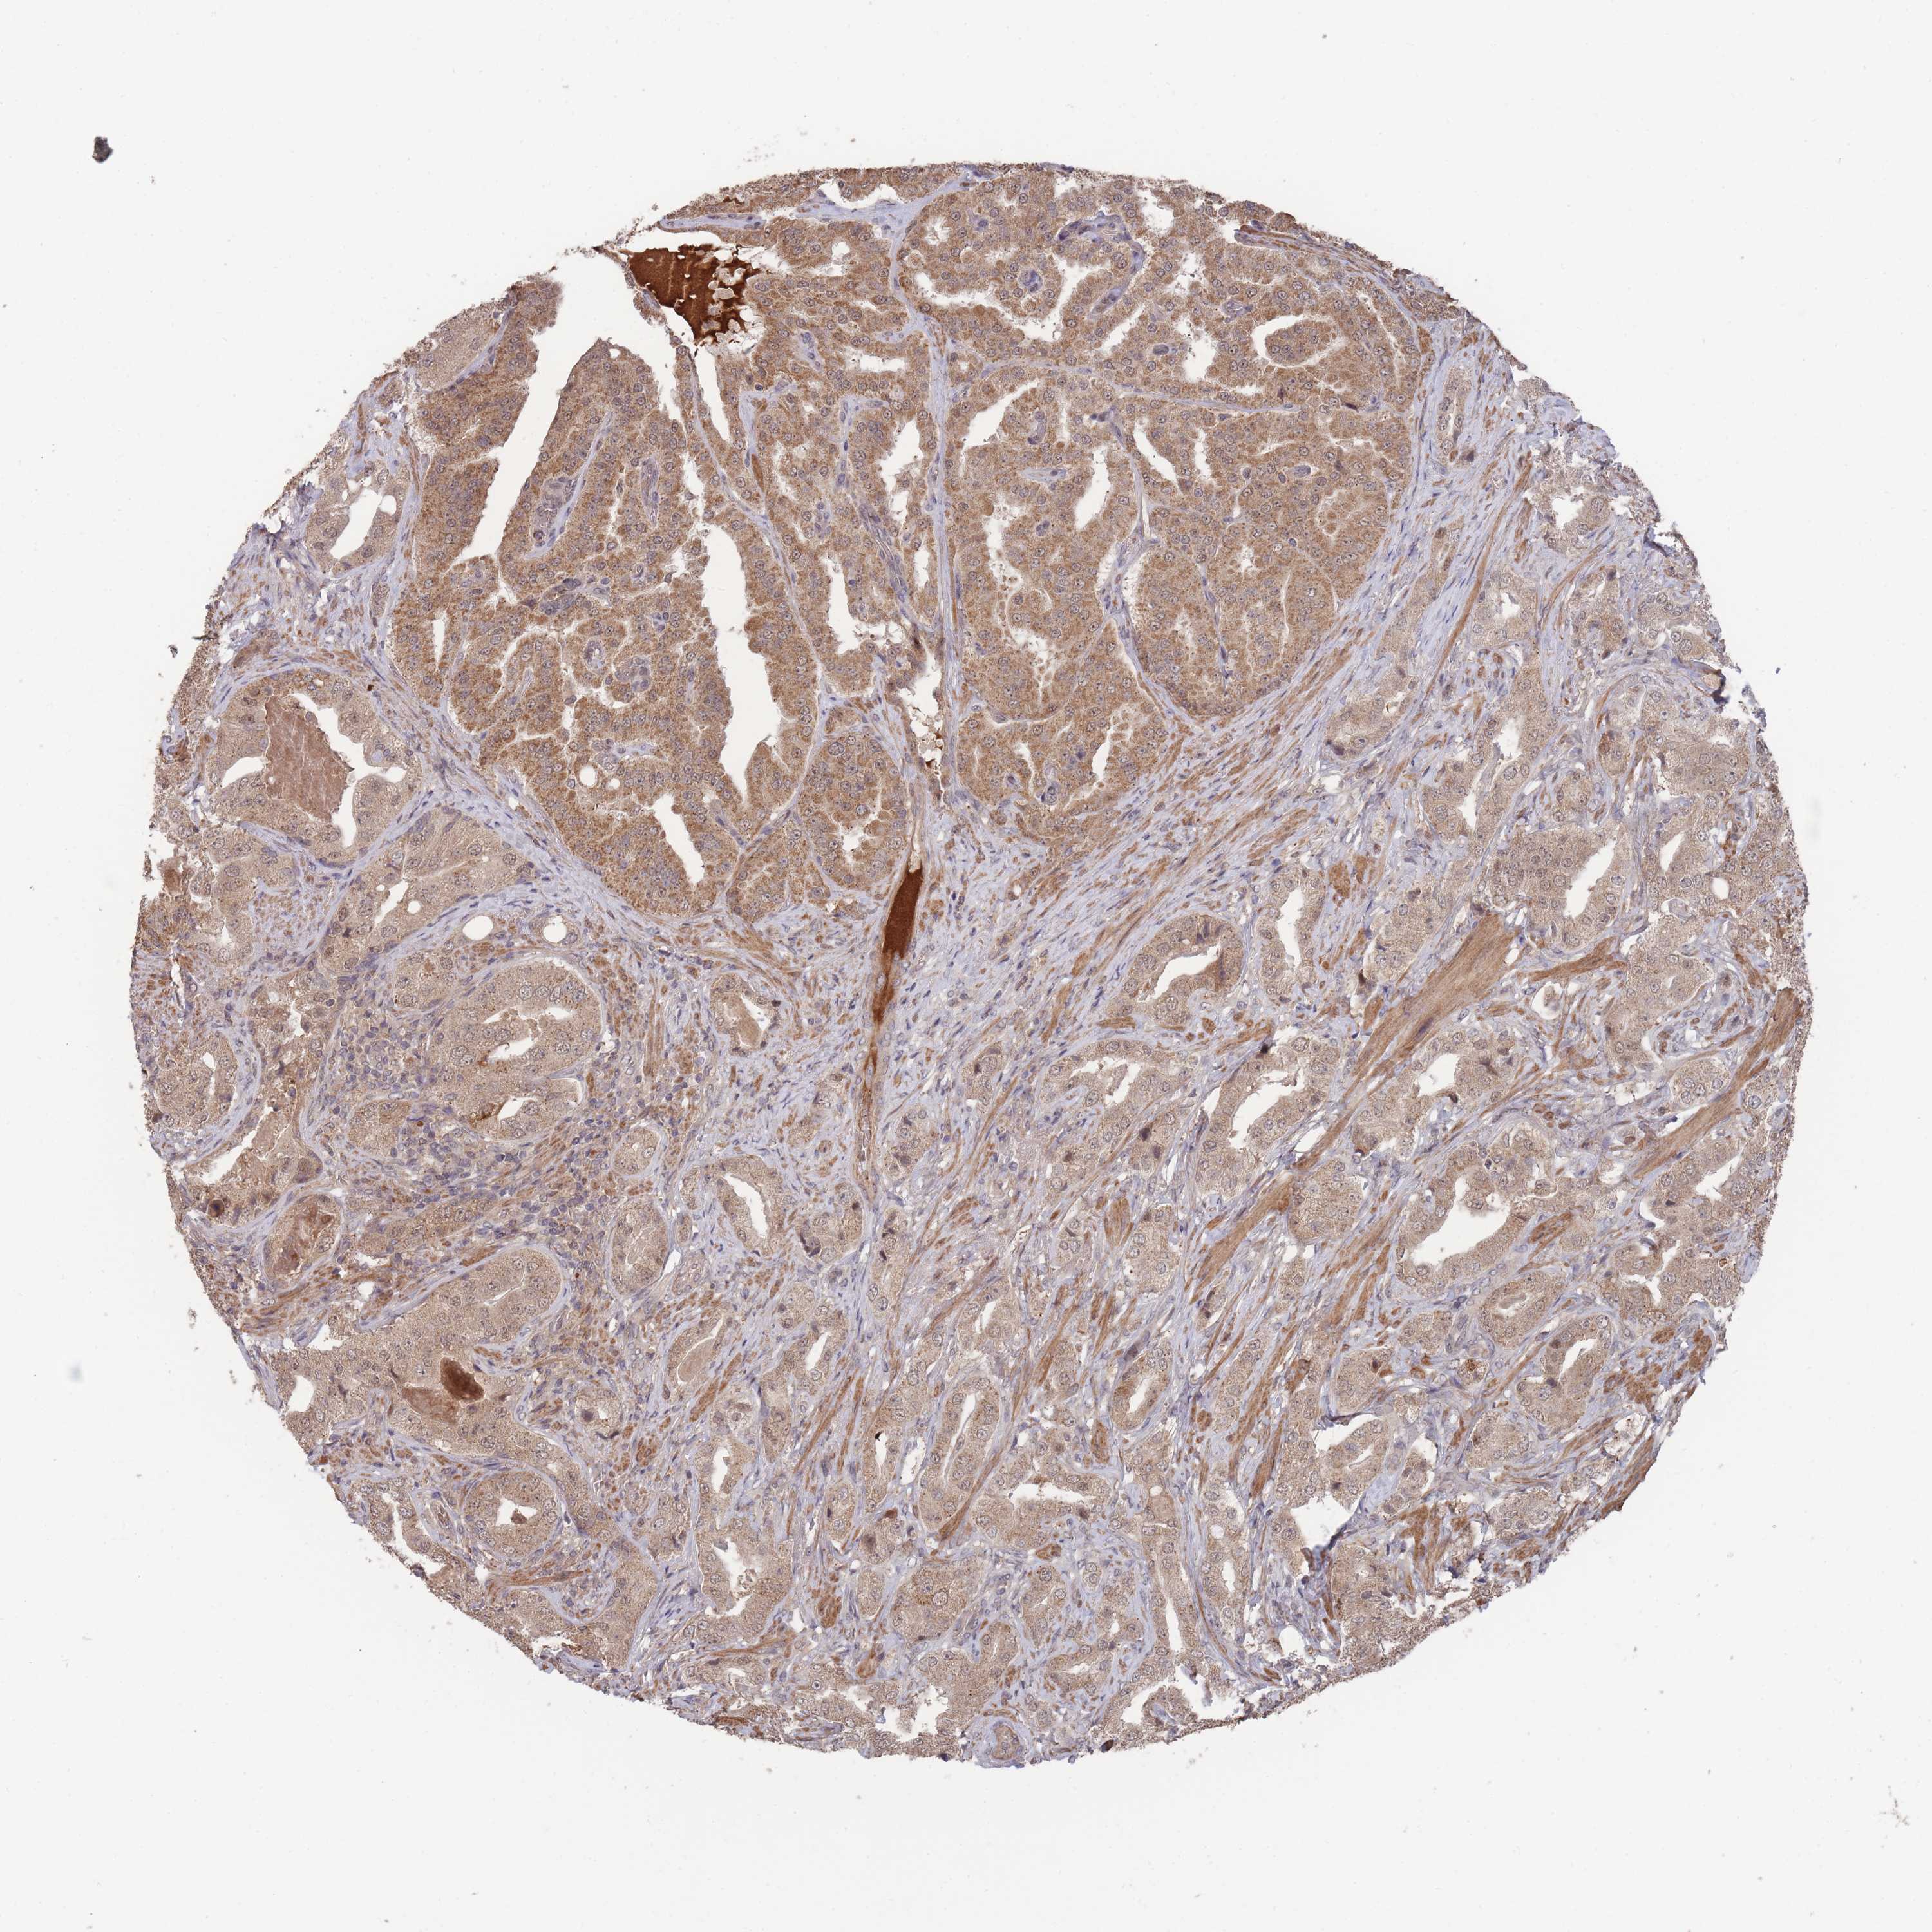

PROSTATE CANCER - Protein expressioni

A mouse-over function shows sample information and annotation data. Click on an image to view it in a full screen mode. Samples can be filtered based on level of antibody staining by selecting one or several of the following categories: high, medium, low and not detected. The assay and annotation is described here.

Note that samples used for immunohistochemistry by the Human Protein Atlas do not correspond to samples in the TCGA dataset.

Antibody stainingi

Antibody staining in the annotated cell types in the current human tissue is reported as not detected, low, medium, or high, based on conventional immunohistochemistry profiling in selected tissues. This score is based on the combination of the staining intensity and fraction of stained cells.

Each image is clickable and will lead to virtual microscopy that enables deeper exploration of all samples and also displays staining intensity scores, fraction scores and subcellular localization as well as patient and tissue information for each sample.

Antibody HPA050275

Staining

High

Medium

Low

Not detected

Intensity

Strong

Moderate

Weak

Negative

Quantity

>75%

75%-25%

<25%

None

Location

Nuclear

Cytoplasmic/membranous

Cytoplasmic/membranous,nuclear

Adenocarcinoma, High grade

Adenocarcinoma, Low grade